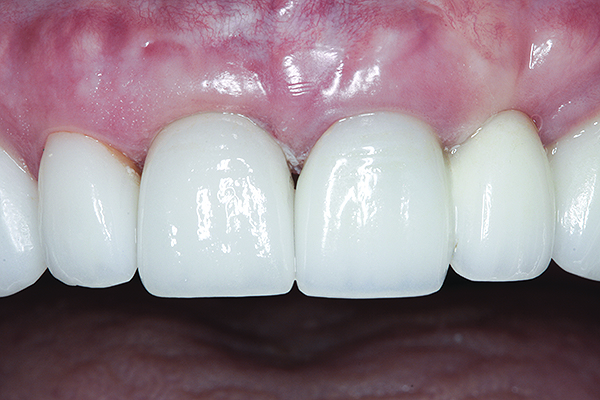

Fig 16. Try-in of the definitive titanium-nitride–coated abutment.

Figure 16

The crown was inserted and secured with a luting composite (Multilink® Automix, Ivoclar Vivadent) (Figure 17); a radiograph confirmed complete removal of excess cement (Figure 18). At the 4-month follow-up appointment, the soft tissues were healed within normal limits, and the patient was pleased with the esthetic outcome of the definitive restoration (Figure 19 and Figure 20).